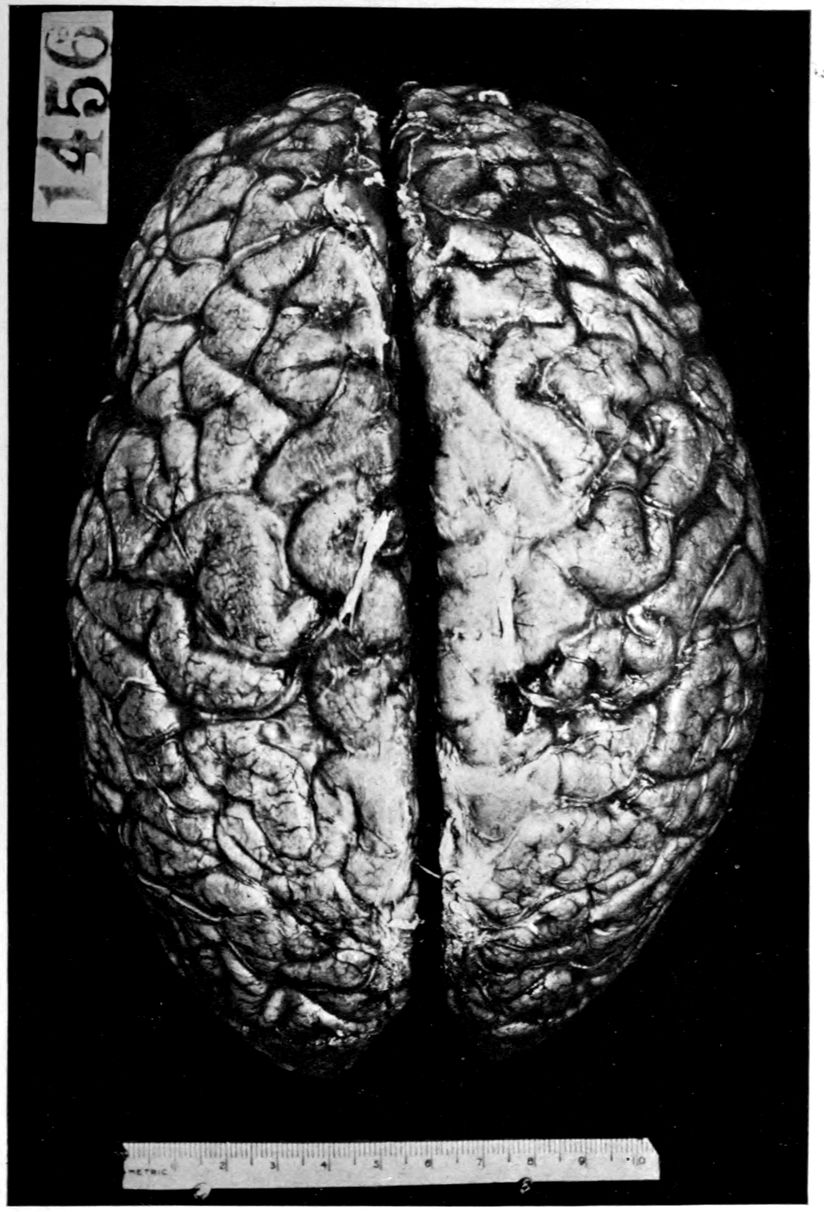

The calvarium was dense and the dura mater thick and adherent. There was a chronic leptomeningitis, which, however, was rather unusual in being most marked in the posterior cisterna and along the sulci of the cerebellar hemispheres. There was a general cerebral sclerosis, with a question of atrophy of the superior temporal gyri (suggesting the so-called Lissauer’s paresis). There was a marked cerebellar sclerosis with a consequent sclerosis (grossly palpable) of the commissural fibres of the pons. There was a generalized slight spinal sclerosis. As a fair sample of the variety of head findings in paretic neurosyphilis, the details of the head examination are presented.

39Crown bald, with a slight fuzzy growth of short hairs. Scalp slightly adherent to calvarium; latter of usual thickness but denser than normal. Dura adherent to calvarium in region of vertex; dura not remarkable. Sinuses normal. Arachnoid villi moderately developed. Pia mater a trifle thickened and rather evenly throughout the cerebral portion. Linear sulcal markings are remarkable for their absence. The wall of the cerebellomedullary cisterna is thick and opaque. The most prominent pial thickenings are over the cerebellum. These are linear or may show feathery out-growths and are seated over the sulci, particularly in the neighborhood of the fissure and about the great cerebellar notch. They correspond fairly well with the focal variation in consistence of underlying tissues noted below.

Brain weight, 1265 grams. Consistence somewhat increased throughout and somewhat evenly increased. The prefrontal region shows the maximal increase of consistence but the remainder of the frontal region and corresponding occipital region are much firmer than normal. The two superior temporal gyri appear to be firmer than adjacent gyri and are possibly slightly diminished in superficial diameter. The hippocampal gyri are fairly firm. The substance on section is a trifle more moist than normal. The gray and white matter cut quite evenly. Diminution in depth of gray matter, if existent, could not be demonstrated. The ventricles show a moderate sanding throughout, best marked in the fourth ventricle. The basal ganglia are not remarkable except for the development of numerous dilated perivascular spaces about the lenticulostriate vessels. The pons is atrophic, but more so on the right side. The pons, like the prefrontal cortex, shows on section a distinct increase of consistence immediately beneath the pia mater. The white bands of the pons on section are distinctly firmer than the intervening substance. The olives are of equal consistence. Weight of cerebellum, pons, and medulla, 155 grams. The cerebellum shows an obvious atrophic and gliotic process of a symmetrical character. The superior surface, including both vermis and hemispheres, shows a consistence above normal and general reduction of the depth measured from the white matter. The reduction in depth gives rise to a visible depression as compared with tissue posterior to the postclival sulci. The lobus cacuminis, though slightly raised from the surrounding lobes, is equally firm, if not firmer. The superior and inferior surfaces show practically an equal increase of consistence. The dentate nuclei are not especially increased in consistence. The flocculi are reduced in size about one-third.

Parenchymatous losses have led to Atrophy and Sclerosis, of very varying extent in different parts of the encephalon. The atrophy is characteristic in paretic neurosyphilis, but by no means constant. Numerous cases have come to autopsy without clearly defined gross atrophy. Sclerosis is also characteristic and even more frequent than atrophy, doubtless because sclerosis represents an earlier phase of a process eventuating in gross atrophy.

Head: Calvarium of moderate thickness; diploë present; dura slightly adherent over bregmatic region. Longitudinal sinus contains cruor clot. Dura is somewhat thickened and slightly more opaque than normal. Pacchionian granulations, small but fairly numerous. Pia contains throughout a considerable excess of clear 44serous fluid. The convolutions in general are of good breadth and proportion. There is an atrophic area roughly circular in outline and about 2 cm. in diameter in the posterior part of the right third frontal convolution corresponding to Broca’s area on the opposite hemisphere. The space thus formed is filled with edema held by the pia. On the left side is a similar subpial collection which covers the site of the posterior portions of all of the third frontal convolutions, parts of the lower end of the precentral convolution, and the whole of the first temporal convolution, which have disappeared entirely. The basal vessels show slight changes.

Vascular neurosyphilis—effects of syphilitic thrombosis of Sylvian artery 10 years before death. (Case 4.)

Head: Scalp closely adherent to calvarium. Calvarium heavy without diploë. Dura adherent to calvarium in bregmatic region. Sinuses contain liquid blood. Arachnoidal villi in considerable quantity. Pia mater contains considerable clear fluid and shows diffuse haziness and focal thickenings. The diffuse haziness is almost universal and is best marked over the superior surface of the cerebellum. The focal thickenings are of general distribution over the veins of the sulci on the superior surface of the brim and are heaped up to form considerable linear mounds near the region of the arachnoidal villi. The superior surface of the cerebellum is traversed by similar linear mounds of fibrous tissue running at an angle to the laminæ. There is no notable increase of fibrous tissue at the base.

Brain: Weight 965 grams. The sulcation is roughly symmetrical except in the occipital poles where there is unusually rich and complex but shallow sulcation. The cortical substance is everywhere firmer than normal, but the sulci fail to flare notably. In a few places there is a focal increase of consistence of still greater degree with apparent local hypertrophy (or gliosis with increase of substance). These foci are in the right second temporal gyrus (3 cm. in diameter) and in the left first temporal gyrus (of same size but somewhat less firm) and are of a whitish, waxen appearance, being visible several feet away by reason of their color and apparent encroachment upon the adjacent sulci. The foci are sharply limited by the sulci laterally, but pale out gradually before and behind.

The convolutions of the vertex show another type of lesion. The tissue of the greater part of the vertex resembles that of the flanks and base in being firmer than normal and of a grayish pink color. Behind the fissure of Rolando on the right side and behind the anterior limits of the ascending frontal region on the left 47side the brain tissue of the vertex becomes suddenly still firmer and of a yellowish gray color. This lesion disappears gradually into the occipital microgyria behind and the gyri gradually lose their yellowish tint. The lesion fades away gradually so that it fails to involve the temporal convolutions.